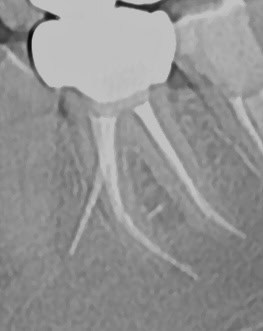

Exemplu: Un premolar doi superior – în mod obișnuit cu un singur canal – a fost tratat de două ori fără succes. Sub microscop s-au identificat trei canale, fapt care explică recidiva. Pe radiografia postoperatorie se observă obturația tridimensională completă a tuturor canalelor și prezența unor puncte albe în treimea rădăcinii, corespunzătoare canalelor colaterale tratate și obturate corect.

Premolarul doi superior, tratat anterior de două ori fără izolare, microscop sau laser, a recidivat. Datorită microscopiei, s-au descoperit trei canale, o raritate (incidență 0,5–1%). Radiografia postoperatorie arată obturația completă tridimensională, inclusiv a canalelor colaterale, realizată cu ajutorul laserului Erbium, care a asigurat curățarea integrală a sistemului endodontic.